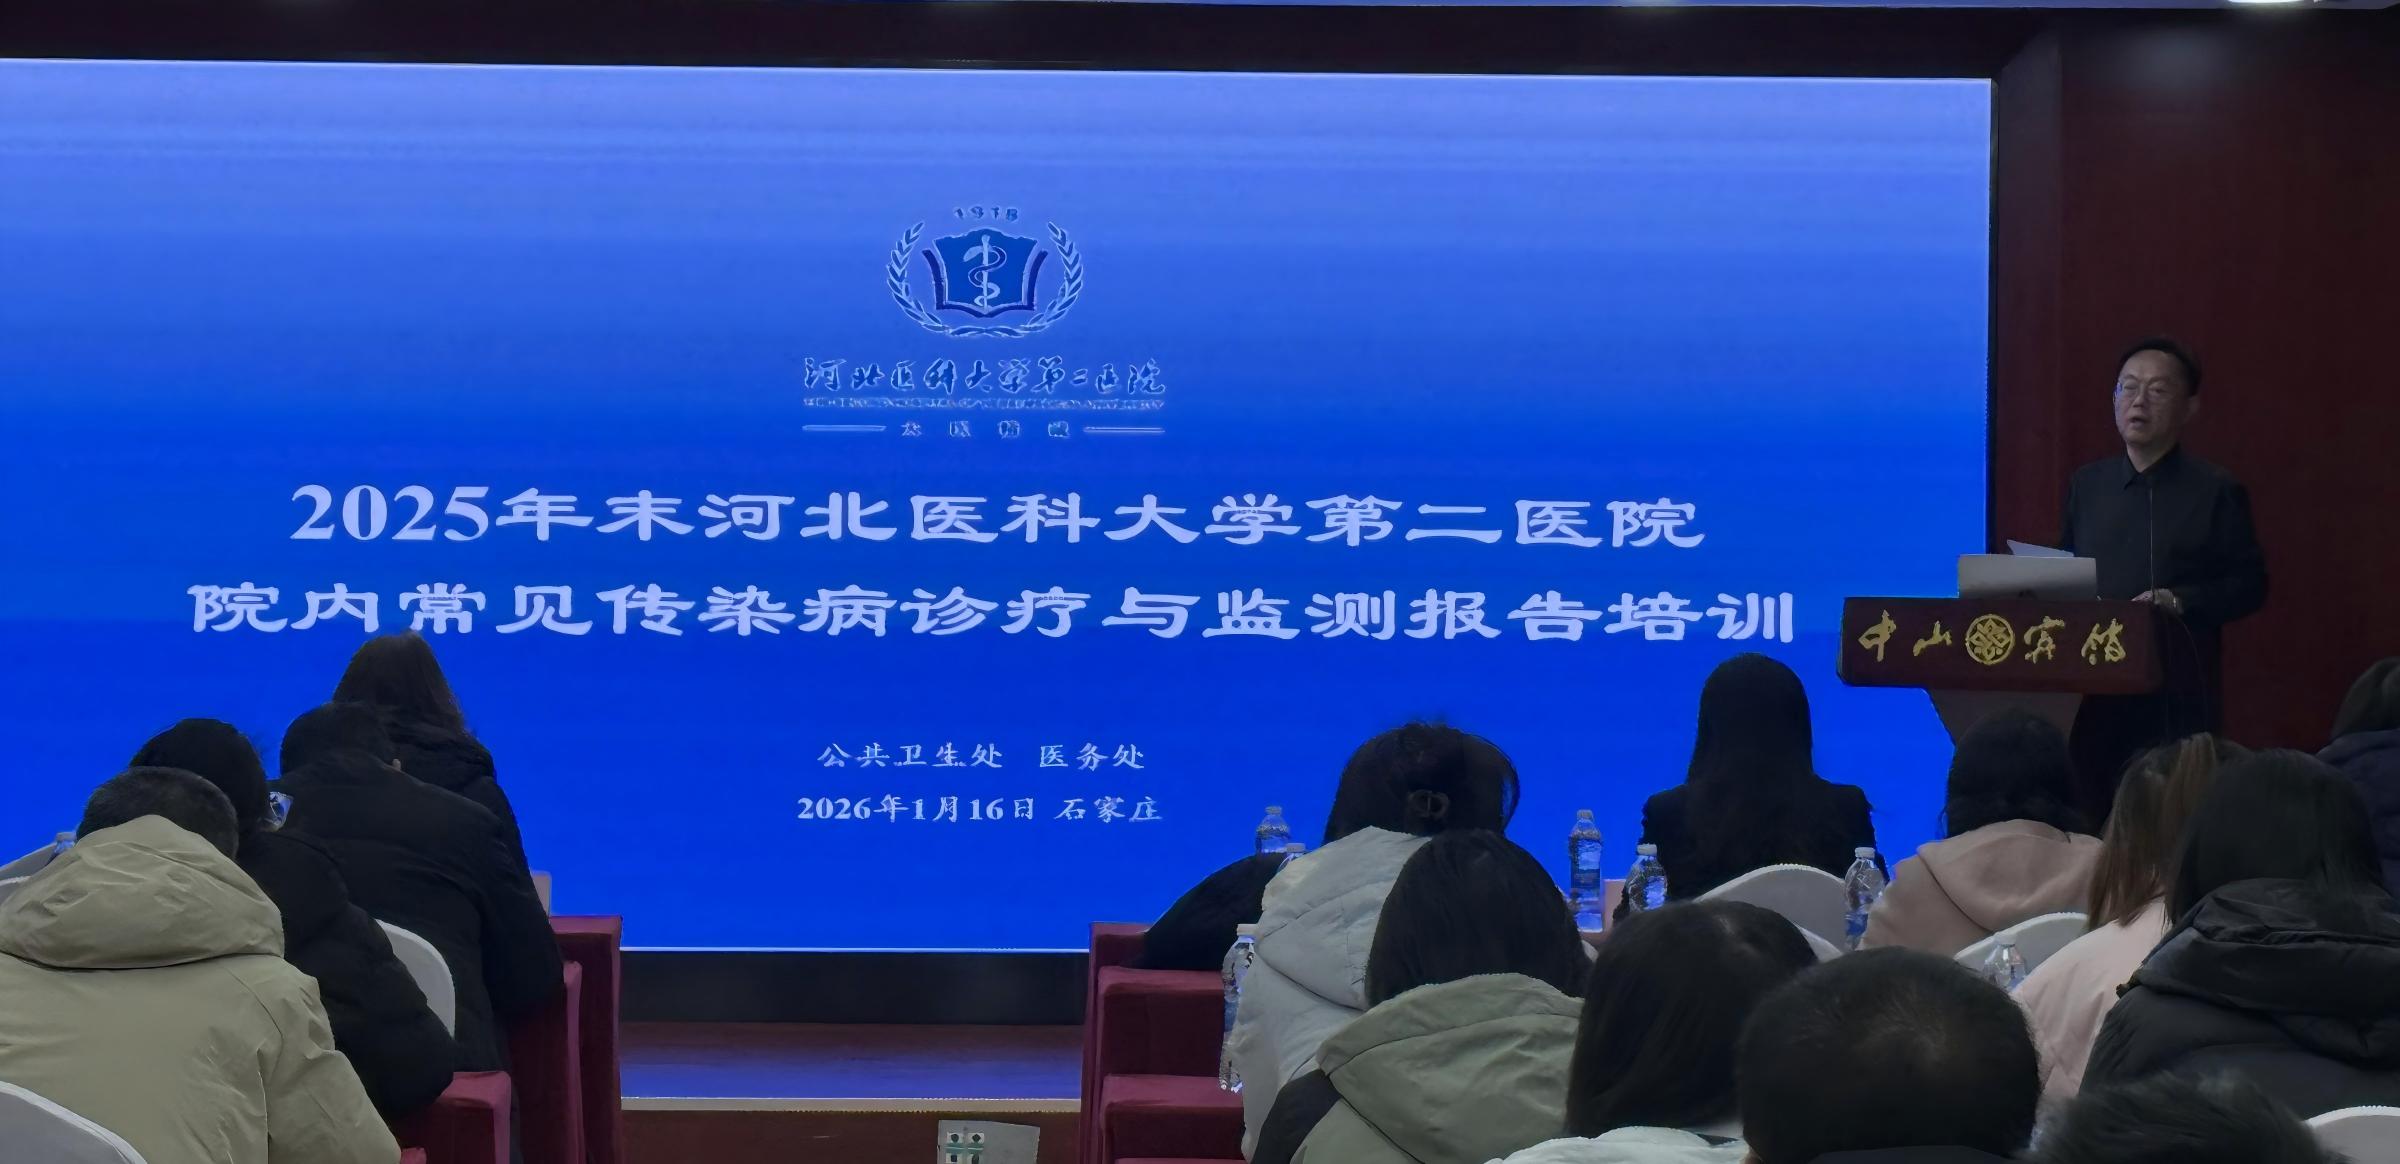

河北医大二院开展常见传染病诊疗与监测培训

为进一步加强我院医务人员对常见传染病的诊疗及防控能力,增强传染病监测预警意识,保障医疗安全,近日,我院公共卫生处与医务处联合组织了两场“院内常见传染病诊疗与监测培训会”。近百名临床一线医生与感控人员参...